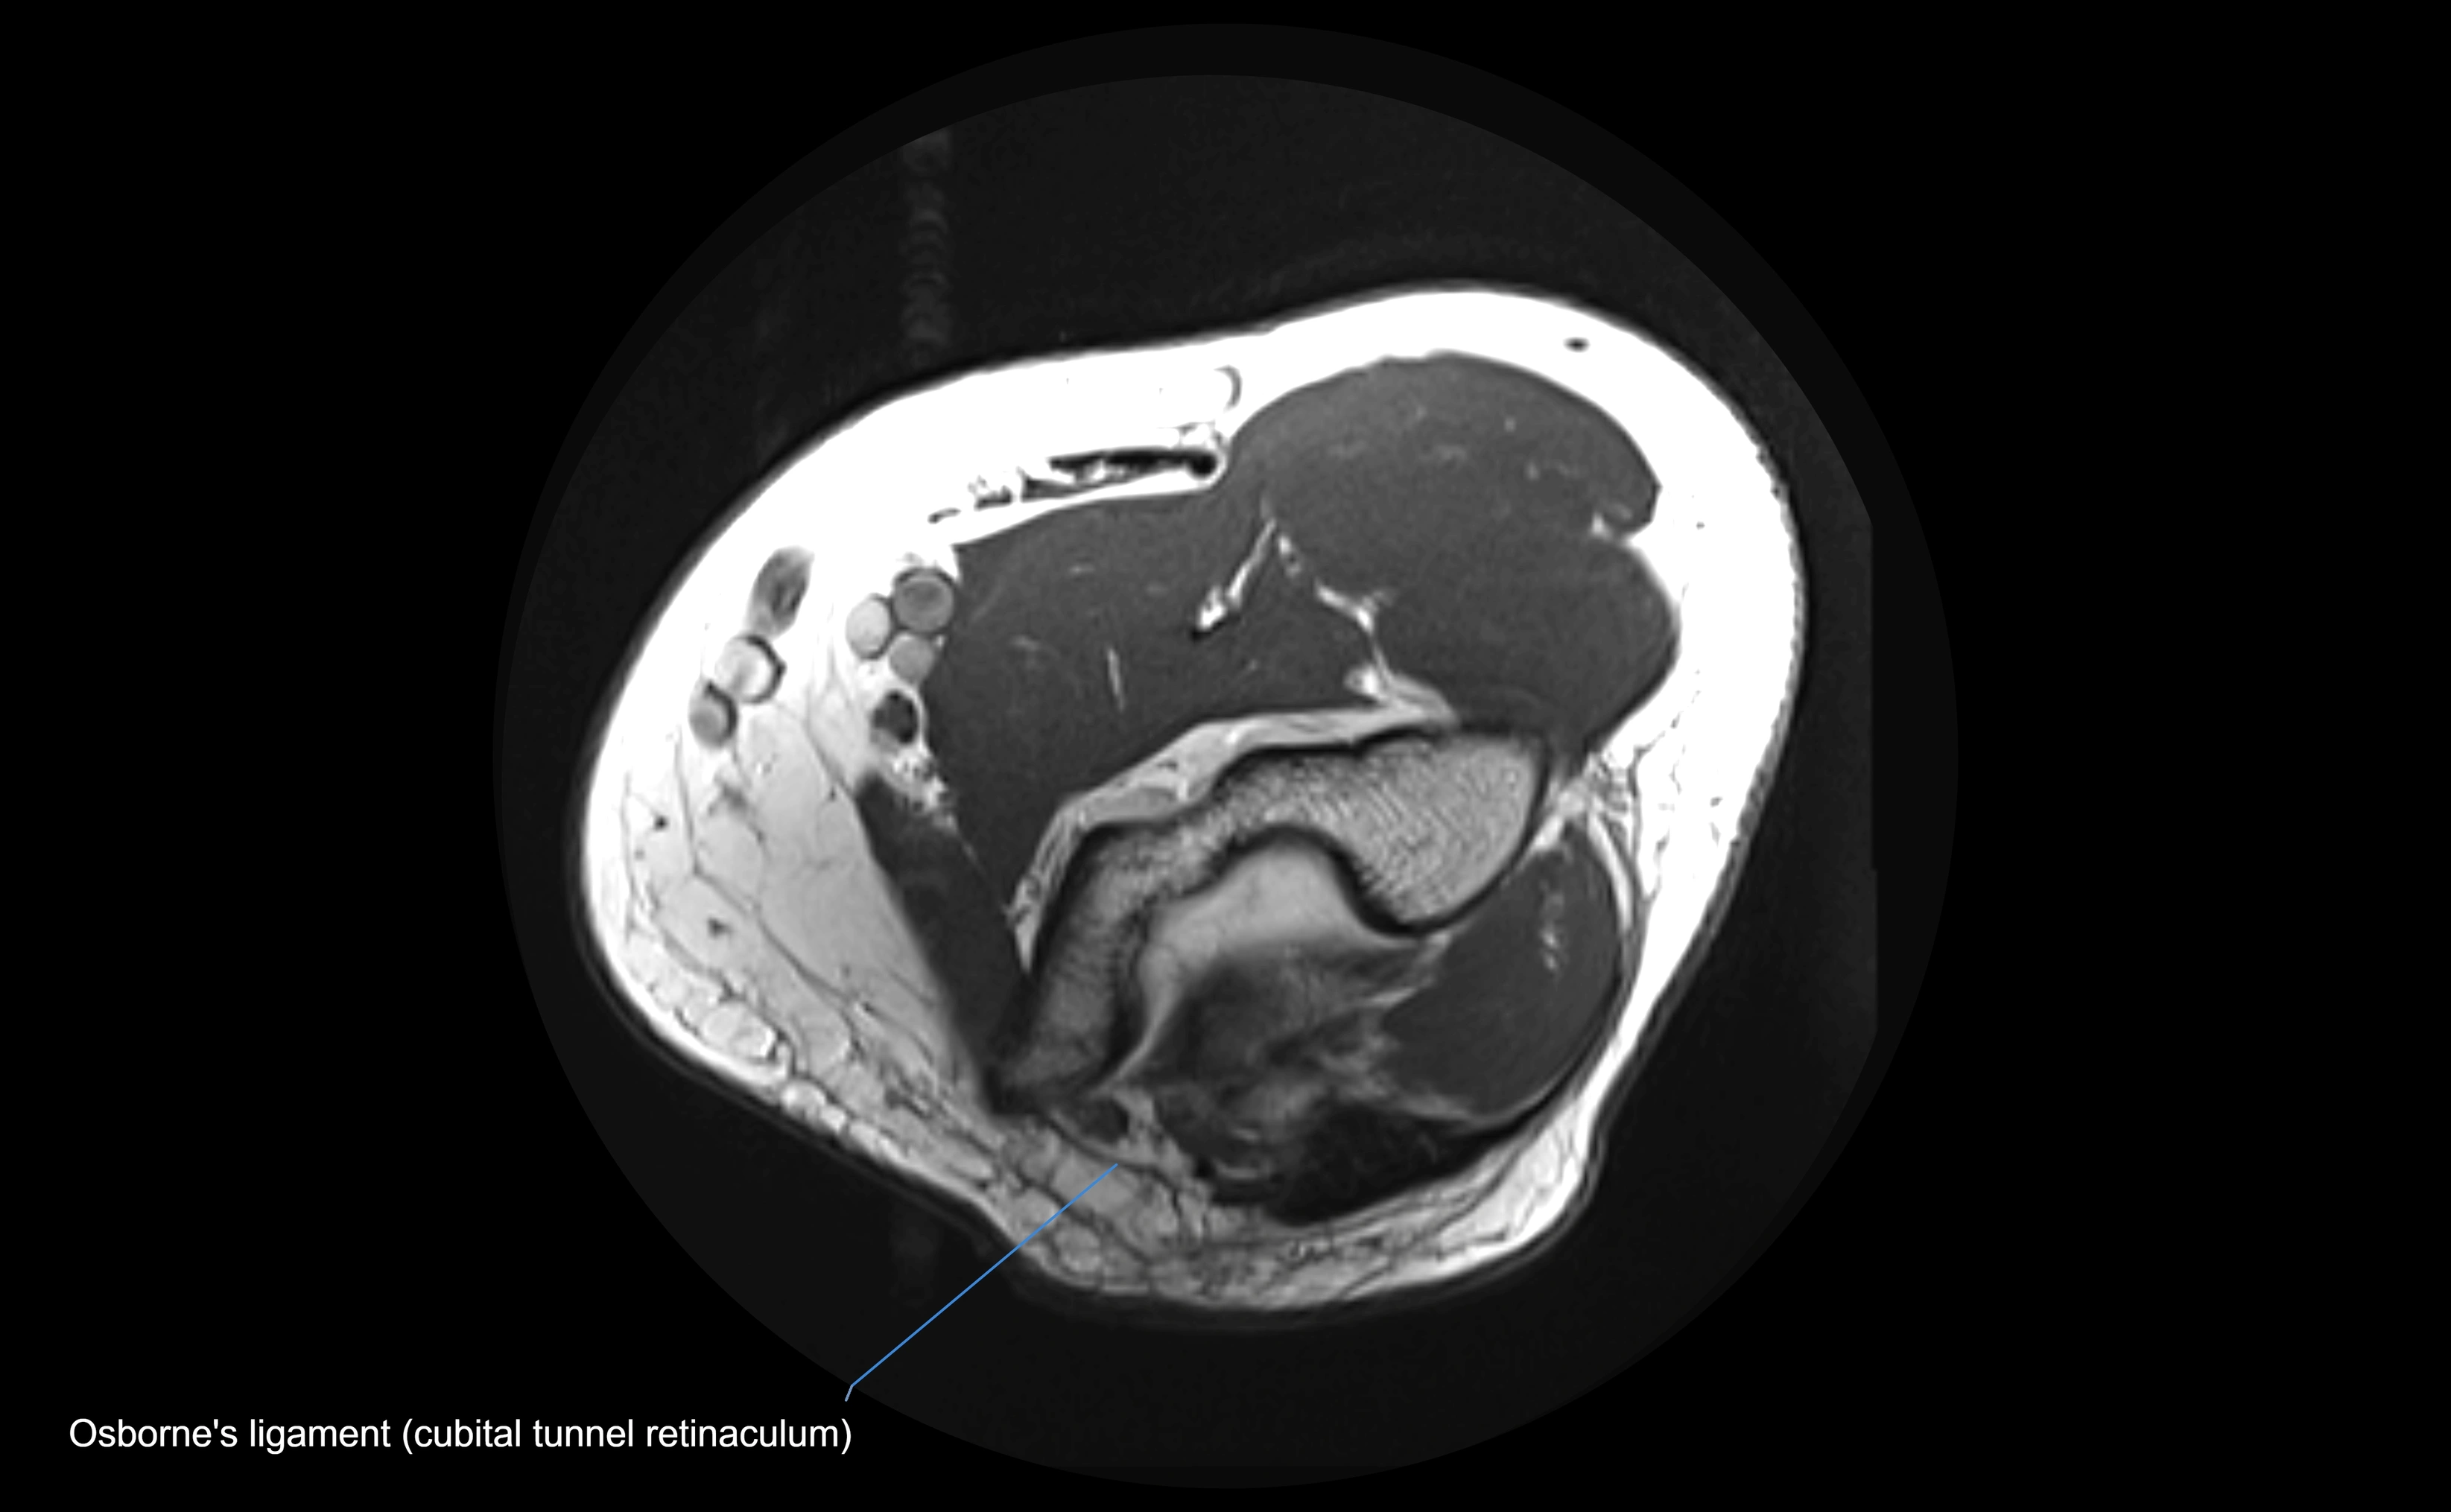

MRI images

image